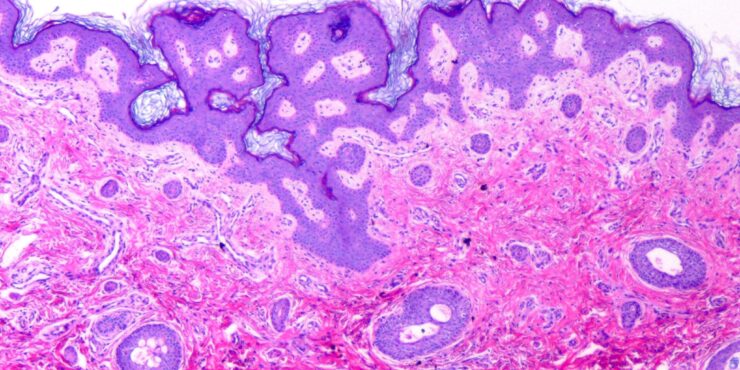

Eosinophilic fasciitis = التهاب الصفاق بالحمضات Eosinophilic Fasciitis Shulman’s Syndrome First described in 1974 , eosinophilic fasciitis is a scleroderma-like disorder characterized by inflammation and thickening of the deep fascia. It has a rapid onset associated with pain, swelling, and progressive induration of the skin leading to exaggerated deep grooving of the skin around superficial […]